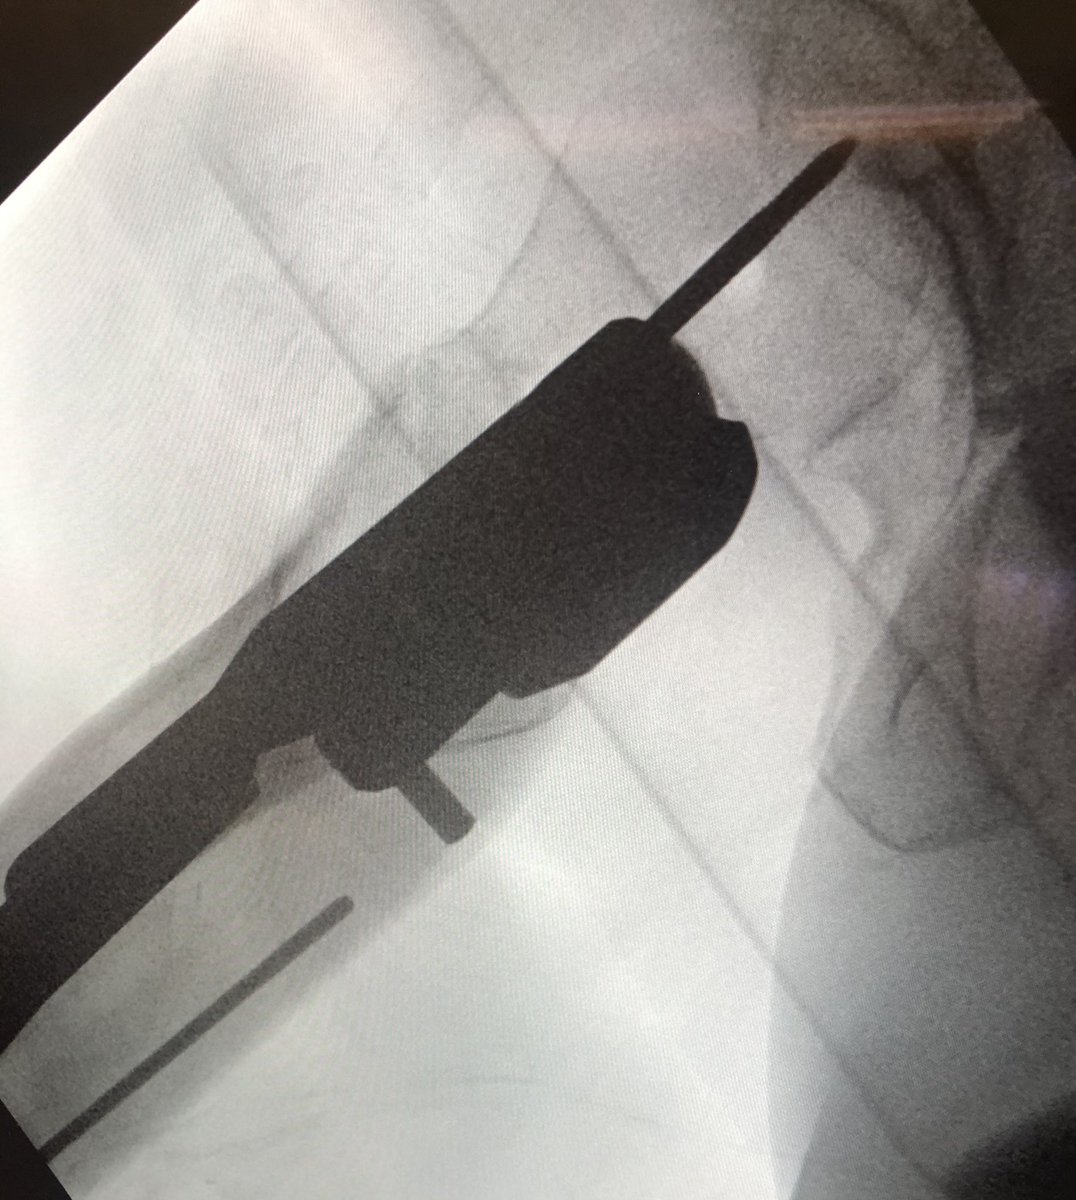

[11/18] I bring wire up to about blue level (I also like to stay inferior, yellow) in order to see it on lateral. Be sure to remove impactor (metal) otherwise will get in way of visual. If I need to change adjustment on lateral, I drill in reverse & redirect wire also in reverse.

[12/18] To see head well, the c-arm has to be sufficiently “wagged” proximally (yellow). Usually that solves most of my problems with lateral. My angle is about 75 deg from vertical in the other plane, to make up for the usual 15 degrees of anteversion (not quite a full lateral).